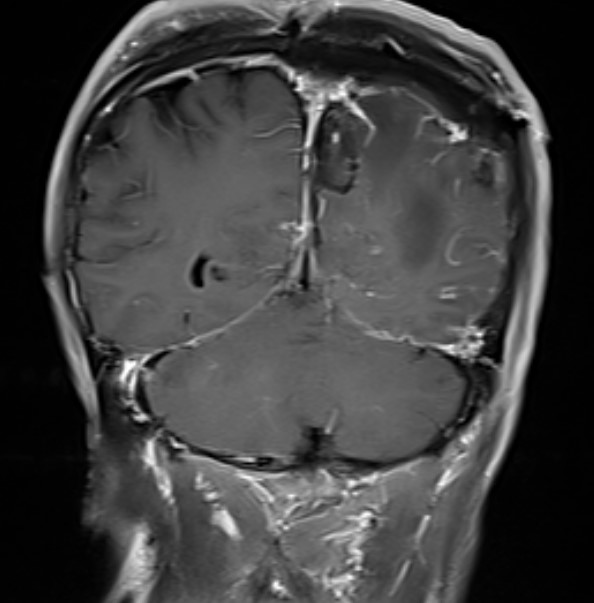

术后MR复查提示肿瘤切除干净